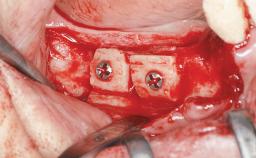

Guided Bone Regeneration (GBR) with a Particulated Autologous Graft and a ePTFE-Reinforced Membrane for Vertical Augmentation of a Single-Tooth Edentulous Space in the Esthetic Zone

Bone Augmentation Staged|Vertical

Augmentation Materials Autogenous chips|Membrane

Bone Volume Deficient vertically or deficient vertically AND horizontally